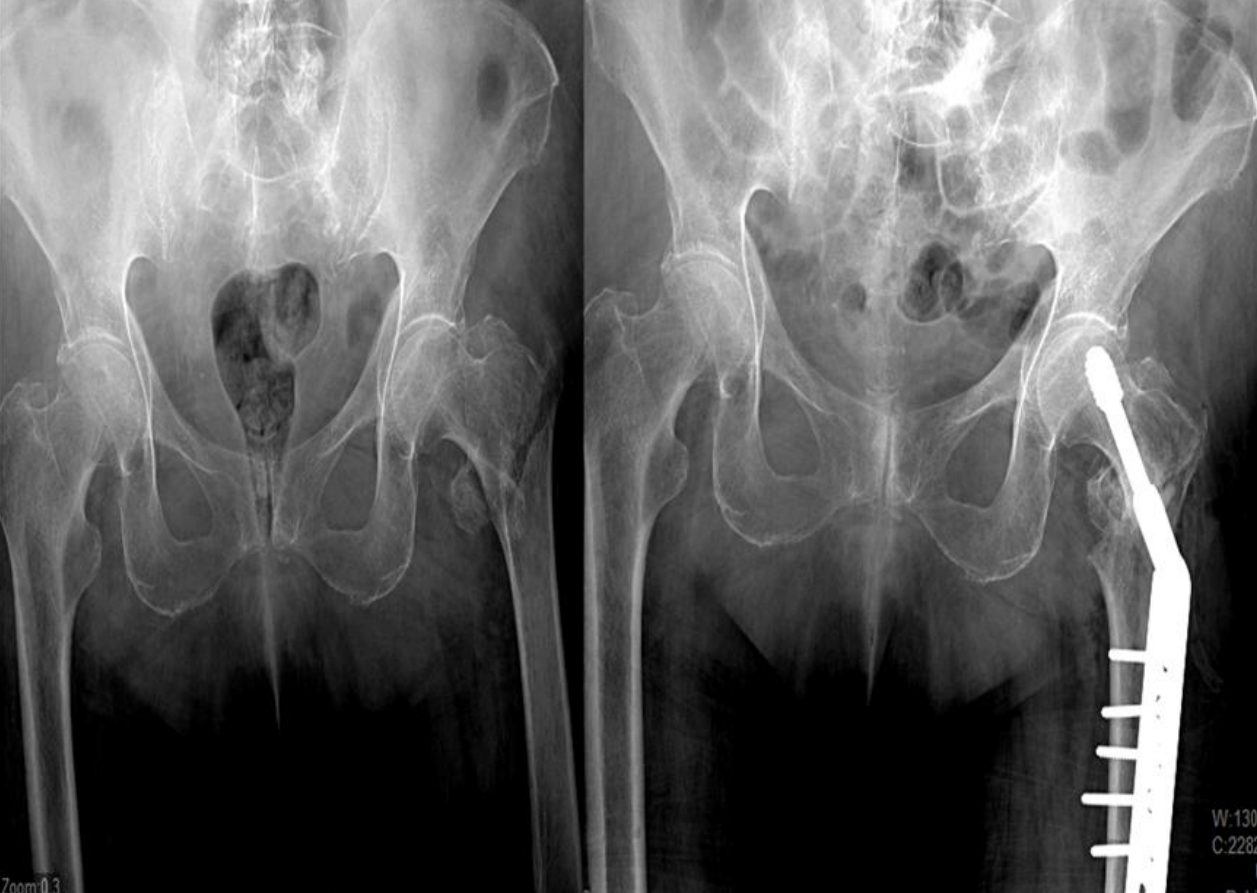

Restaura huesos fuertes y sanos dentro de un marco de tiempo clínicamente relevante

GeneX restaura el hueso a la estructura trabecular normal en 36 semanas

Fractura de la meseta tibial

Postoperatorio

15 meses